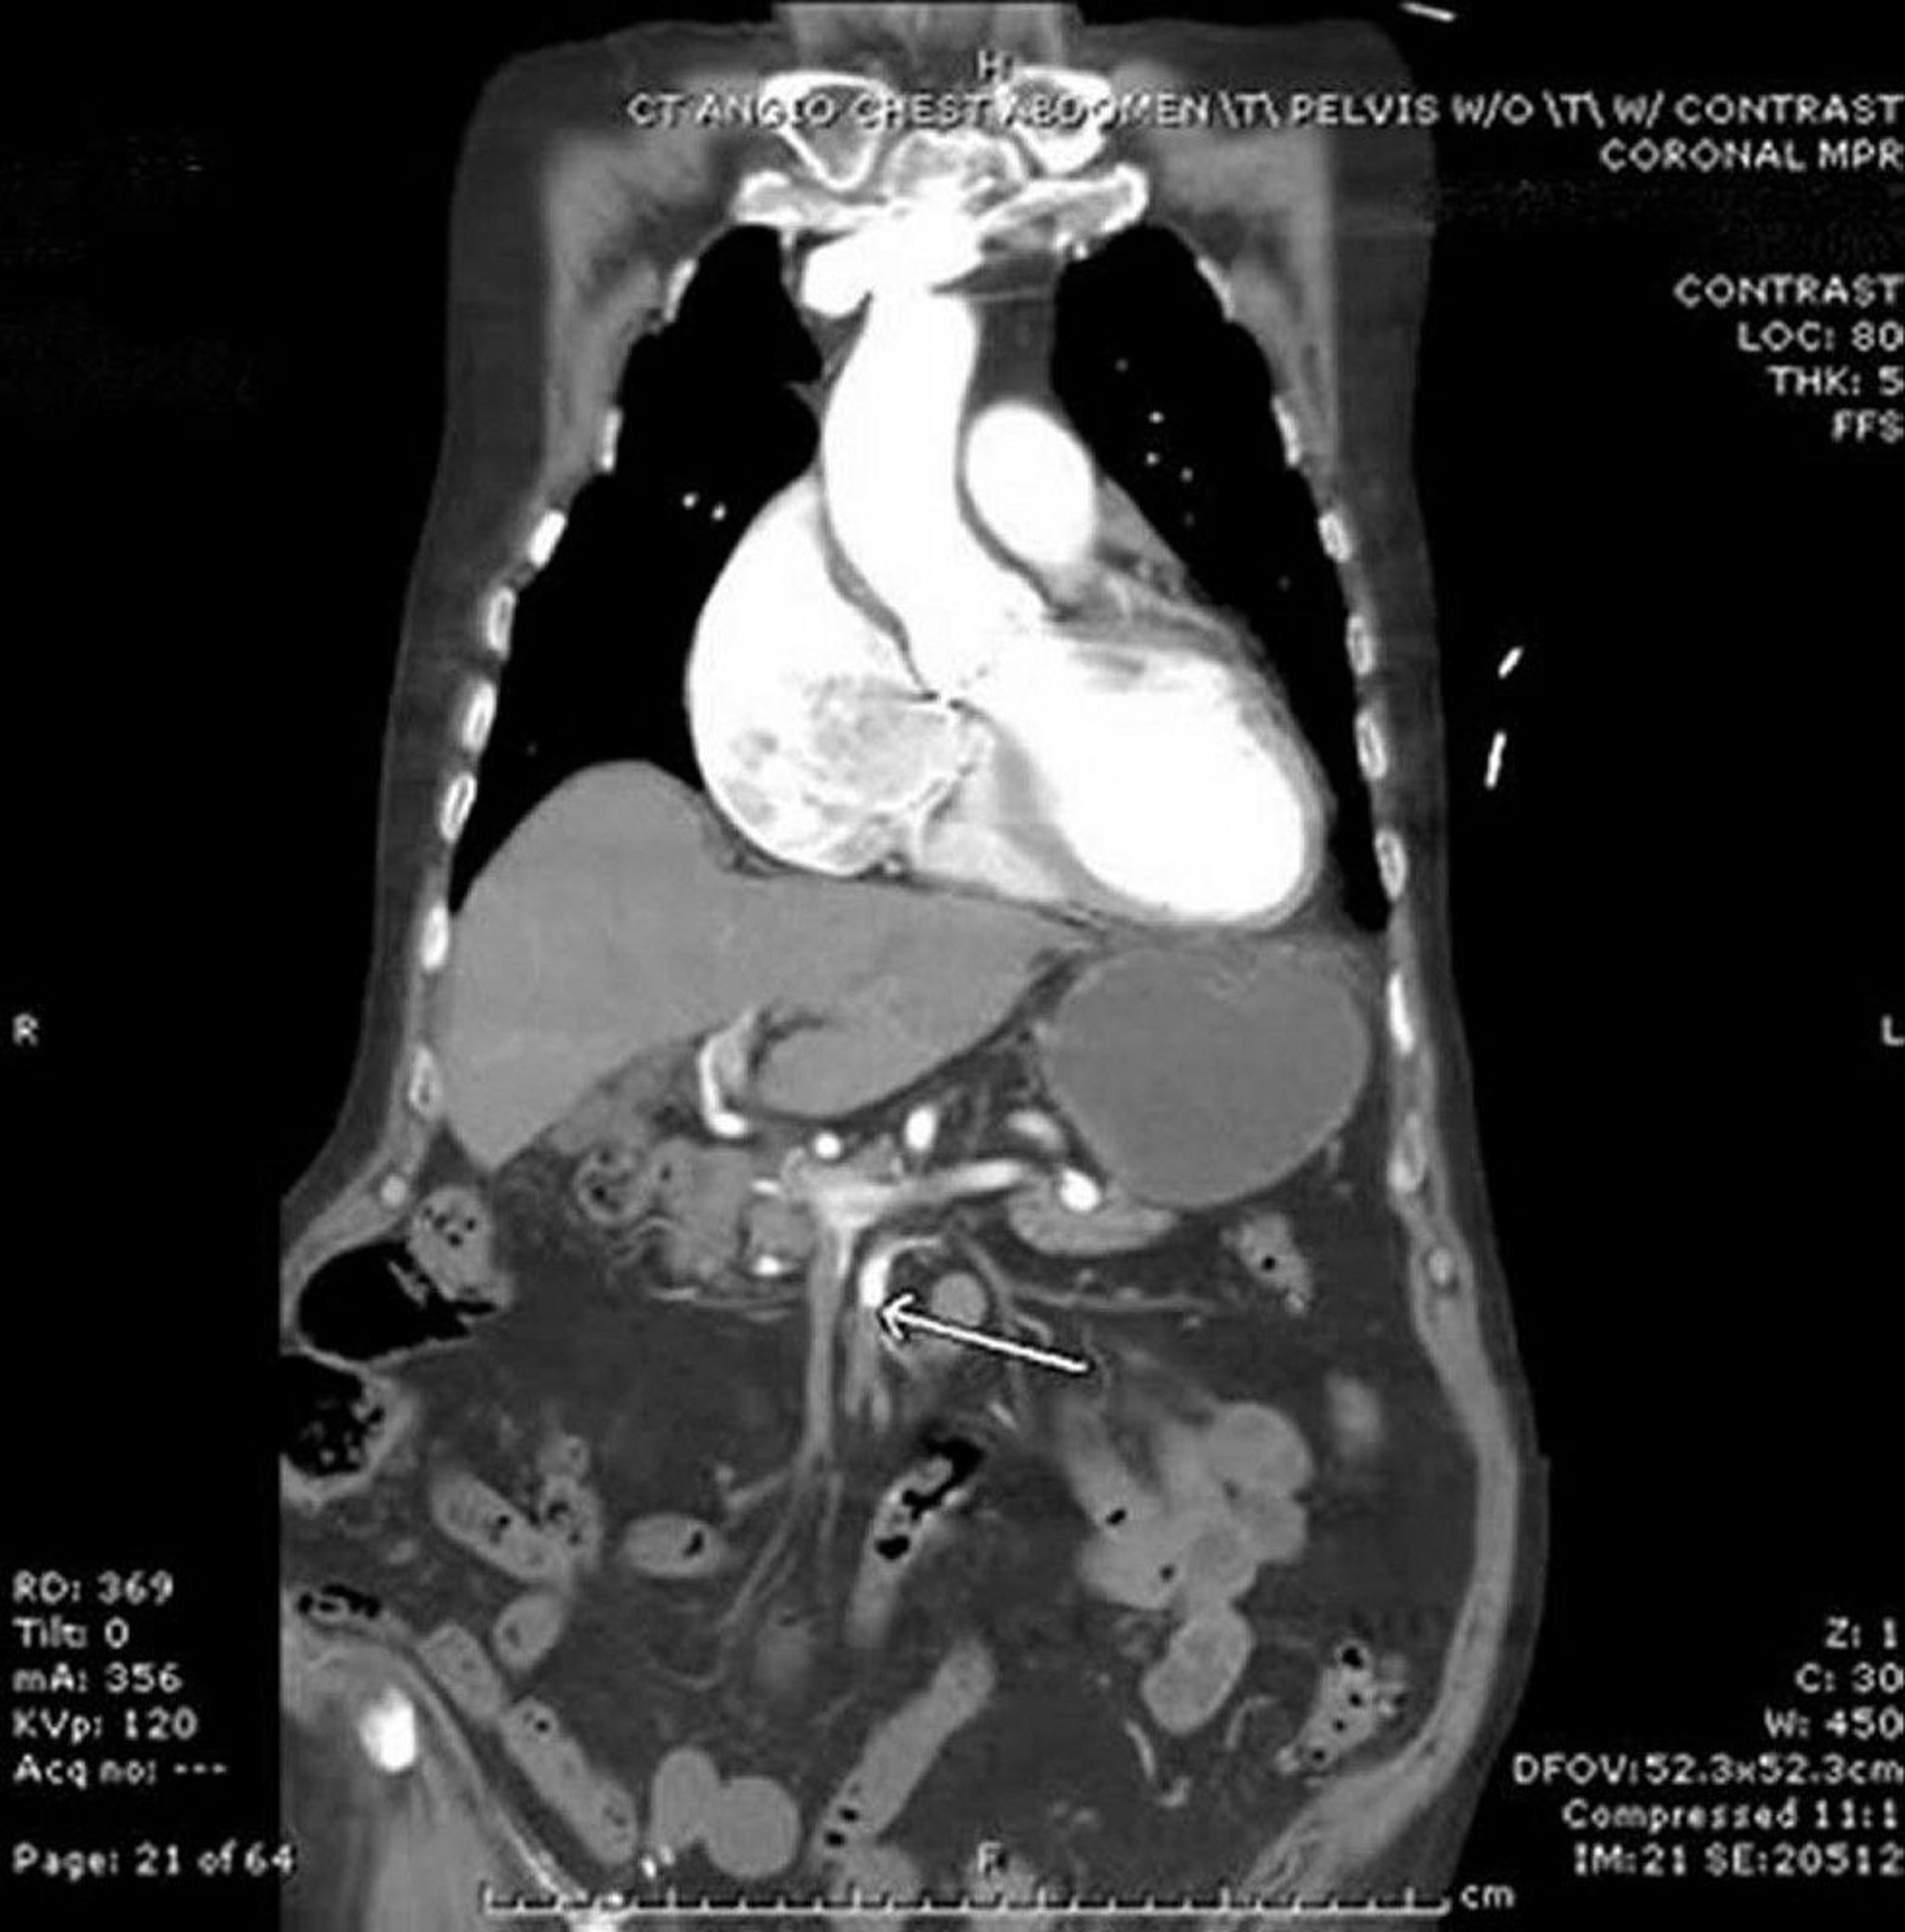

Mesenteriale Ischämie (CT-Angiogramm)

In diesem Bild zeigt der Pfeil auf die Arteria mesenterica superior, die einen abrupten Abbruch des intravenösen Kontrastmittels aufweist. Es ist eine Verdickung des Dünndarms im linken Bauchraum zu sehen. In diesem Fall handelt es sich um eine Embolie aus dem Herzen bei einem Patienten mit Vorhofflimmern.

Image provided by Parswa Ansari, MD.